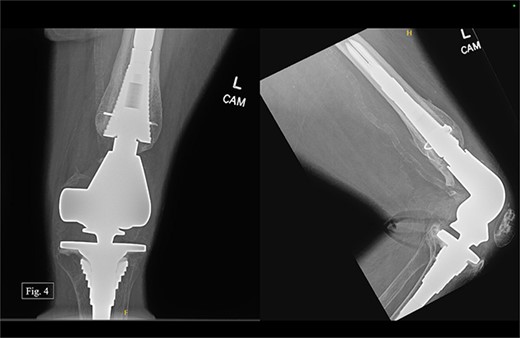

The patient presented to our level 1 trauma center in September 2022 with acute right knee pain and unable to ambulate. She was seen and evaluated in the emergency department, where she was found to have evidence of a right distal periprosthetic femur fracture (Su Type II) after a ground-level fall (Fig. 5). Because of the open box configuration of the native TKA implant and adequate available bone stock, a standard Stryker right retrograde intramedullary nail (IMN) was selected.